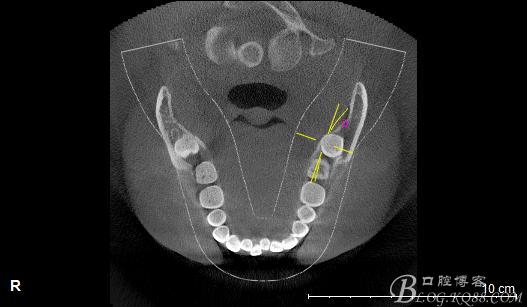

一、術(shù)前CBCT影像資料